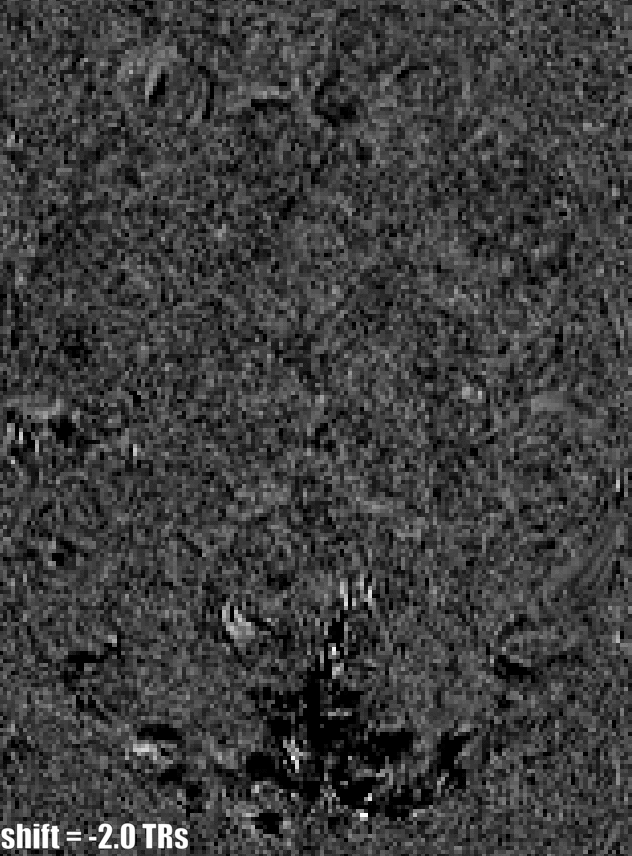

VASO time courses with a large spectrum of shifts applied. Which one does represent the most reasonable looking time course? The transient-horns are getting stronger for larger shifts.